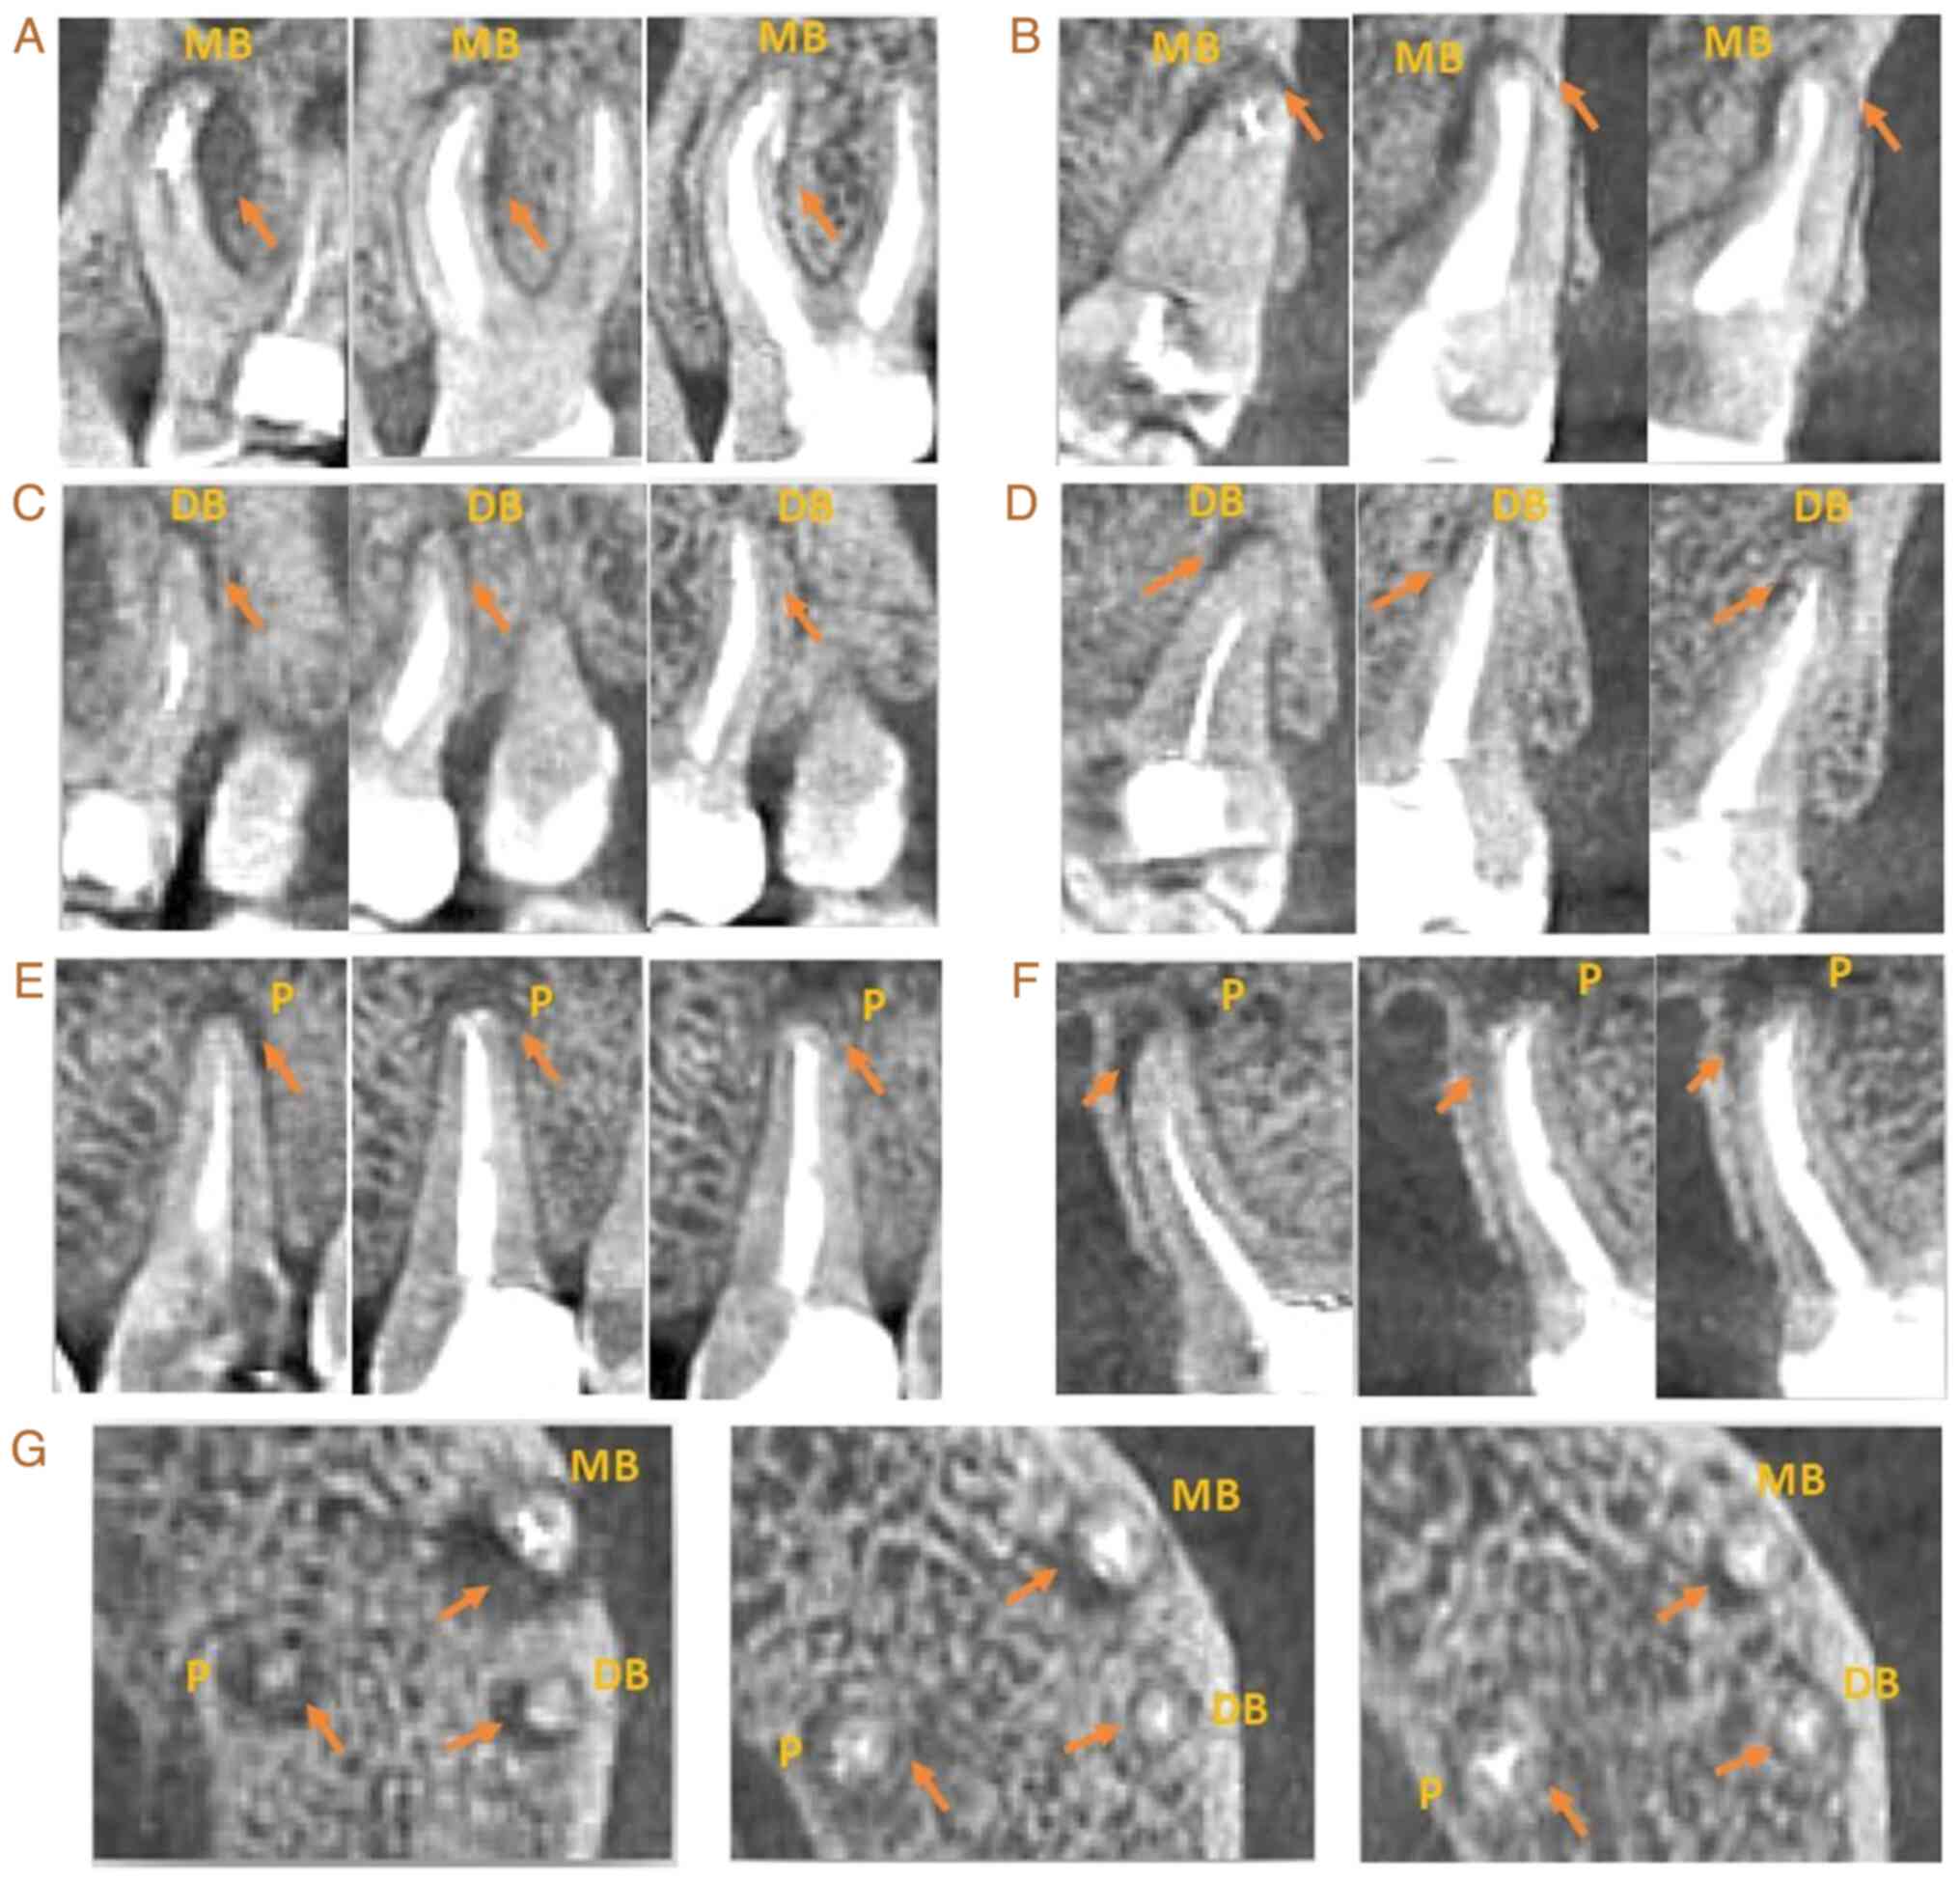

At 9 months after surgery, CBCT revealed that the hypodense area surrounding the DB, MB and P root apex had significantly diminished (Fig. 2). At 27 months after surgery, CBCT revealed that the hypodense areas surrounding the DB, MB and P root apex almost completely disappeared (Fig. 2).

Figure 2

Follow-up observation of tooth no. 26 via X-ray. (A) Sagittal X-ray of the MB root. the first was taken before the operation, the second was taken 9 months after the operation and the third was taken 27 months after the operation. (B) Coronal X-ray of the MB root. The first was taken before the operation, the second was taken 9 months after the operation and the third was taken 27 months after the operation. (C) Sagittal X-ray of the DB root. The first was taken before the operation, the second was taken 9 months after the operation and the third was taken 27 months after the operation. (D) Coronal X-ray of the DB root. The first was taken before the operation, the second was taken 9 months after the operation and the third was taken 27 months after the operation. (E) Sagittal X-ray of the P root. The first was taken before the operation, the second was taken 9 months after the operation and the third was taken 27 months after the operation. (F) Coronal X-ray of the P root. The first was taken before the operation, the second was taken 9 months after the operation and the third was taken 27 months after the operation. (G) Cross-sectional X-ray of the three types of roots. The first was taken before the operation, the second was taken 9 months after the operation and the third was taken 27 months after the operation. MB, mesiobuccal; FI, fractured instrument; DB, distal buccal; P, palatal.

At 9 months after surgery, the periapical hypodense areas surrounding the MB, DB and P roots markedly decreased, and the periapical tissue had almost completely recovered at 27 months after surgery.